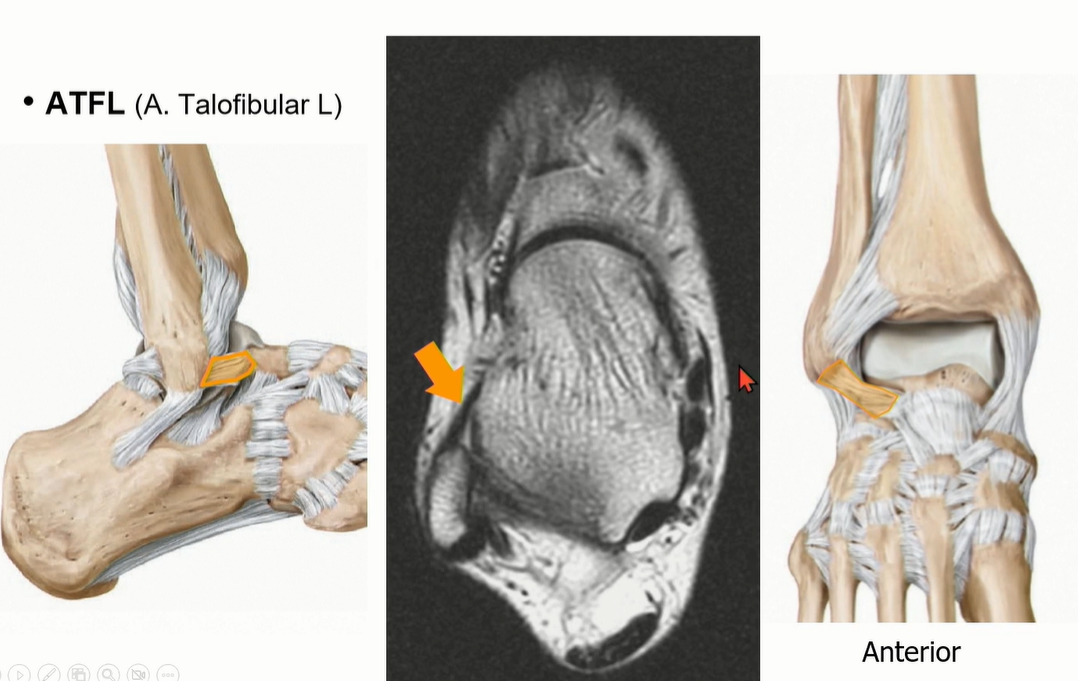

2-1 . ATFL(anterior talofibular ligament)

Double bundle로 되어 있는 경우가 있음을 염두.

ATFL은 Axial cut에서 잘 관찰되며, fibula가 강낭콩 모양인 레벨에서 앞으로 주행하는 것을 찾으면 된다.

(그것 보다 윗 레벨에서는 joint capsule이나 AITFL을 ATFL로 오인할 수 있다)